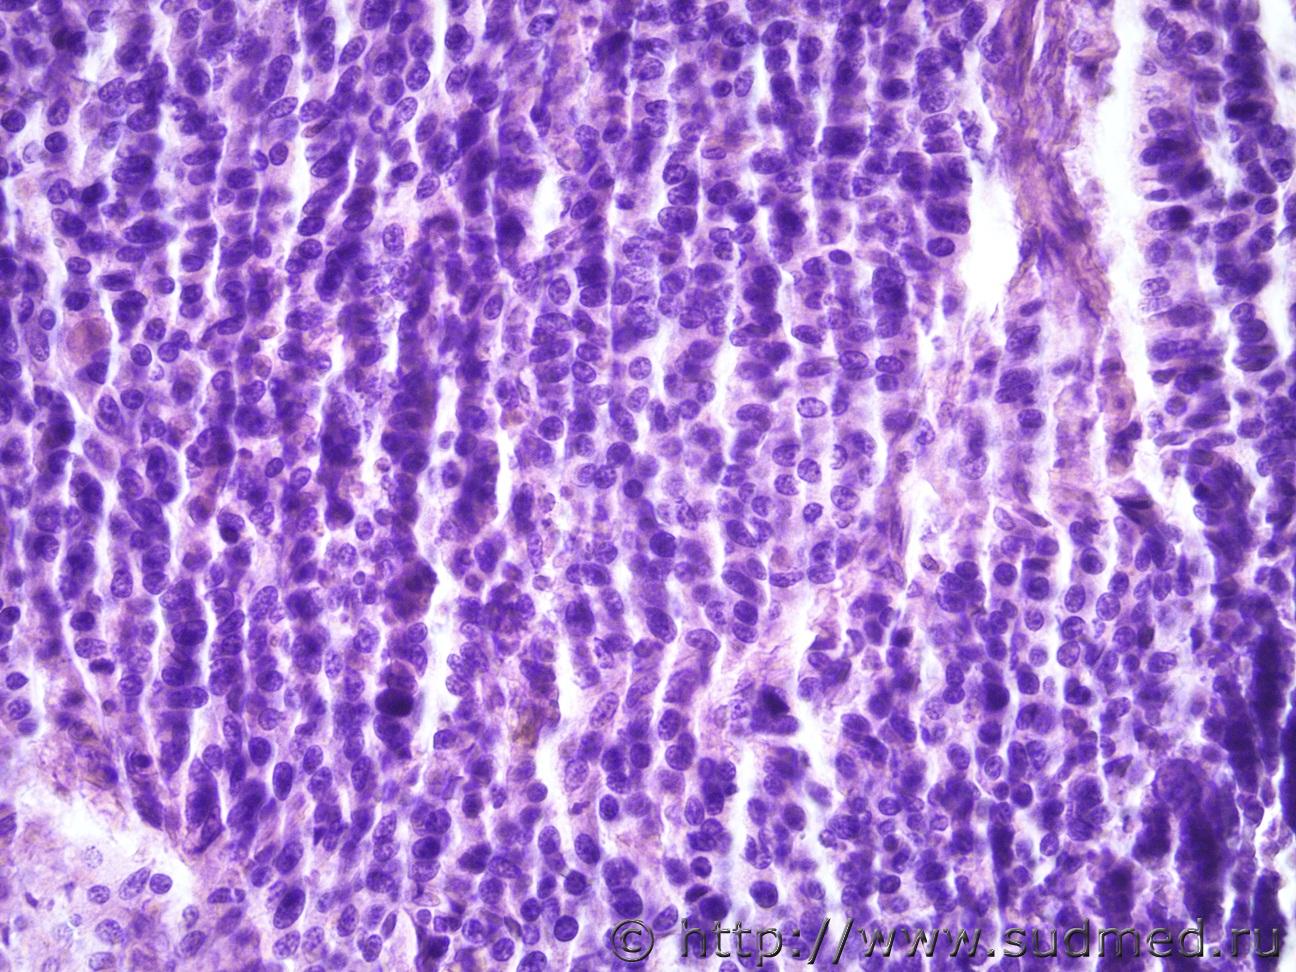

Ув. коллеги, еще опухоль корня легкого. Муж 1957 года рожденияСудебная медицина - Прикрепленное изображение Судебная медицина - Прикрепленное изображениеСудебная медицина - Прикрепленное изображениеСудебная медицина - Прикрепленное изображение

Плоскоклеточный низкодифференцированный рак.